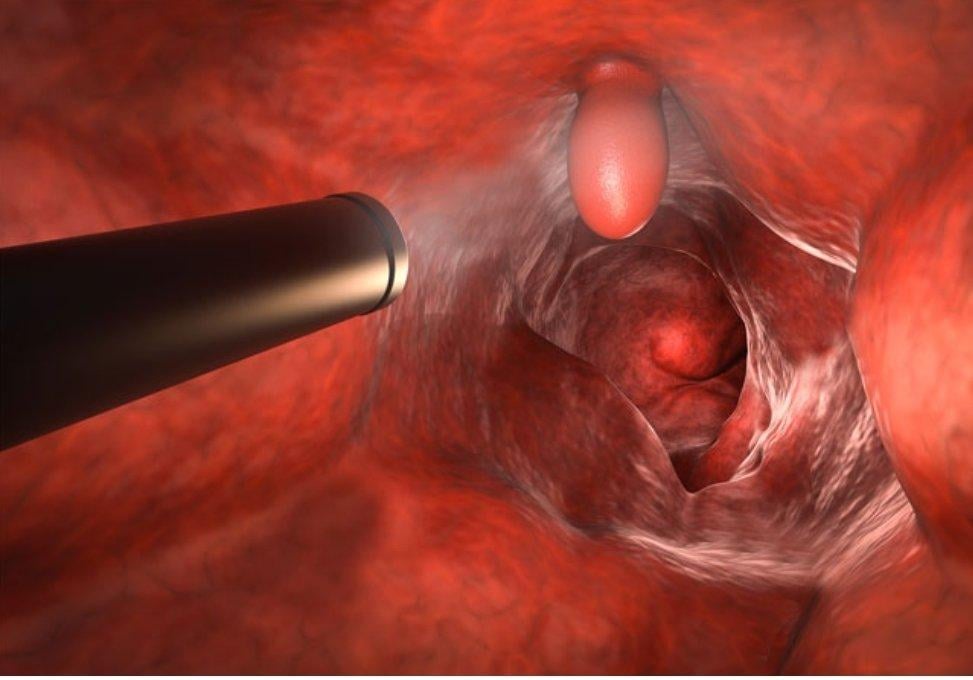

大腸直腸癌台灣發生率第一:早期發現早期治療

醫生建議,有家族史者應於40歲後就開始定期接受大腸鏡檢查,可找出早期大腸癌。

大腸鏡檢查還可找出息肉並切除,預防大腸癌發生。

「有大腸癌家族史,要提早做大腸鏡檢查。」游彥麟醫生指出,一等親有大腸癌家族史、二等親有2人以上罹患大腸癌,罹患大腸癌機率會增加1倍以上,建議有家族史者應於40歲後就開始定期接受大腸鏡檢查,可找出早期大腸癌。